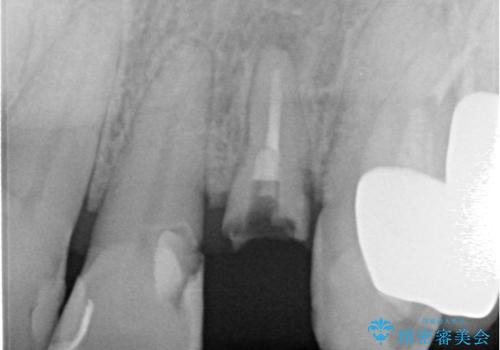

診察をしたところ、歯根に縦破折が認められ、抜歯が必要と判断されました。

抜歯、インプラント埋入、仮歯の装着が同時に可能な1DAYインプラントが適用可能と判断されたため、インプラントによる補綴治療を行うこととしました。

前歯のインプラント治療は、従来の抜歯から数ヶ月待機する手法では、骨造成や歯肉移植など付随の処置が多く必要となり、費用、期間、身体的負担のいずれもが多大となります。

抜歯時にインプラントを埋入することでそれらの負担を大きく軽減させることが可能です。